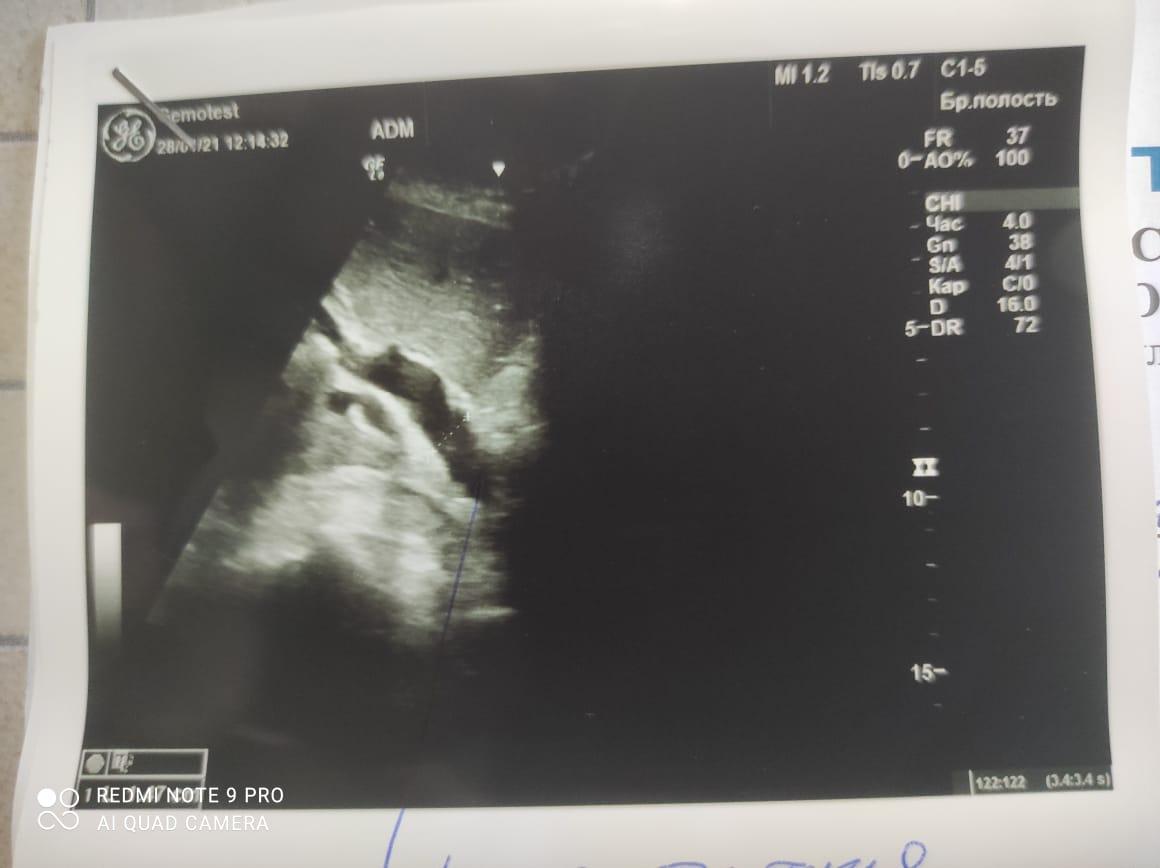

Здравствуйте! При наличии коралловидного камня правой почки(заключение УЗИ), можно предположить причиной боли нарушение уродинамики верхних мочевых путей), что, однако, не подтверждается результатами УЗИ почек( ЧЛС не расширена). Другая, наиболее вероятная возможная причина "боли в боку" - может быть патология опорнодвигательного аппарата. Необходимо проконсультироваться с неврологом и урологом очно, и согласовать возможность применения противовоспалительных, обезболивающих и спазмолитических препаратов - как первый шаг. В дальнейшем необходимо планировать возможное дальнейшее обследование и лечение. Удачи!